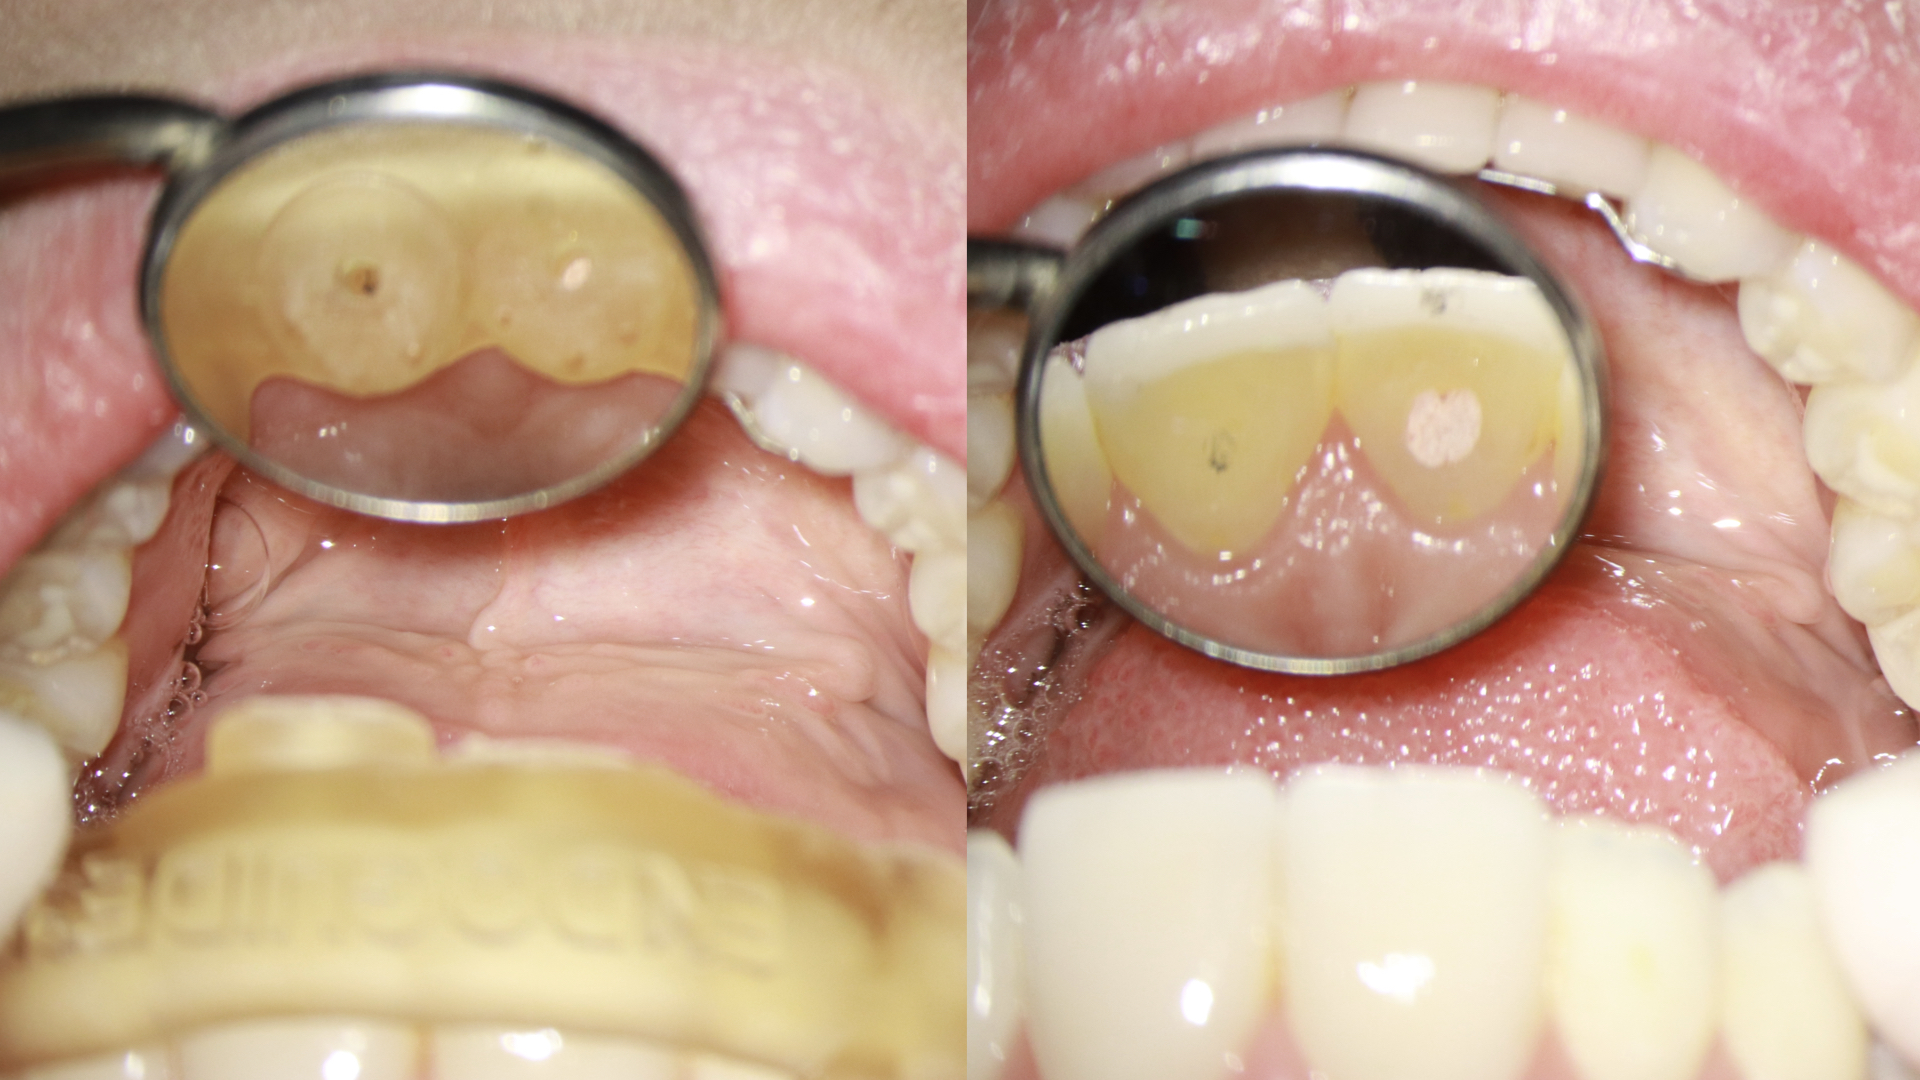

- Prova do endoguide em boca, avaliando a adaptação distal sobre a oclusal dos dentes e também nas janelas que encontramos no guia (figura 4).